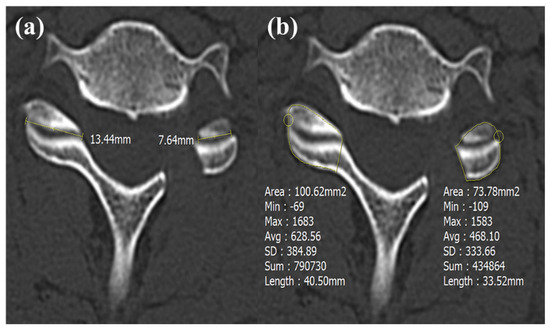

| Foraminal dimension (mm2) | 34.3 ± 8.5 | 31.5 ± 7.8 | 0.16 |

| Post foraminal dimension (mm2) | 54.5 ± 8.2 | 53.3 ± 7.4 | 0.51 |

| Foraminal enlargement (%) | 63.8 ± 26.1 | 75.5 ± 34.6 | 0.13 |

| Facetectomy width (%) | 43.2 ± 7.3 | 51.6 ± 11.3 | 0.01 * |

| Facetectomy area (%) | 40.5 ± 8.1 | 48.1 ± 10.4 | <0.01 * |